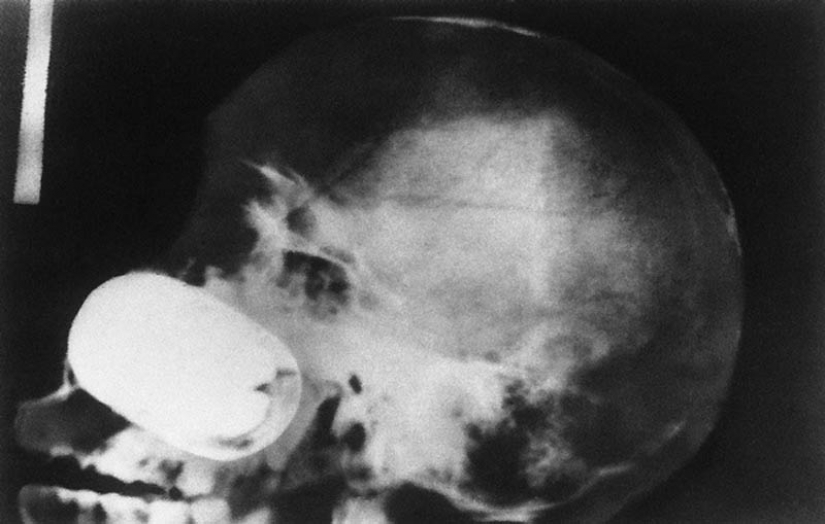

11. La lanza de la arpón, atrapados en la cabeza de un joven de 16 años de edad, niño de pesca.